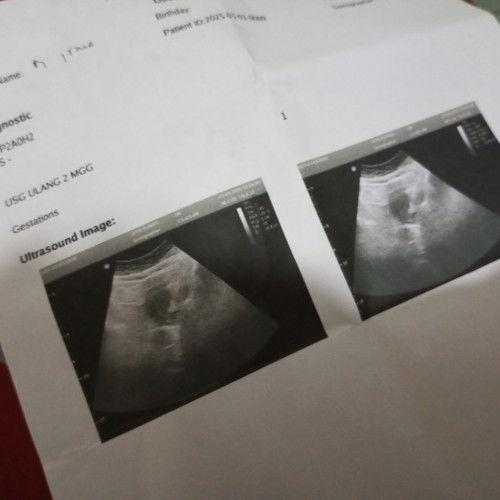

Usg ulang 2 Minggu lagi apa ada yg sama?

Di tespek Alhamdulillah dapat garis 2 TPI stelah ush justru tidak terlihat apa2😭 dan dokter menyarankan agar kembali lagi setelah 2 Minggu untuk memastikan apakah sudah ada kantong janin atau tidak 🥹 Apakah bunda2 yg sudah berpengalaman mngalami hal yg sama ??#mohonbantujawabbunda